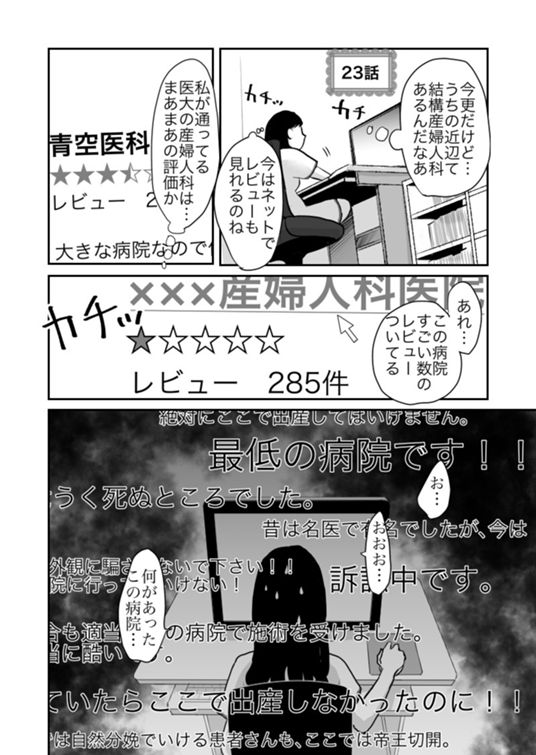

23話 産婦人科の評判